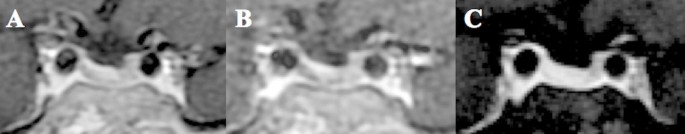

ACTH levels progressively increased as the dose of osilodrostat was escalated (Fig. 2A). After 3 months of biochemical eucortisolism, she underwent Met-PET/MRCR, which revealed a distinct methionine-avid lesion in the right posterolateral aspect of the sella (Fig. 3). Imaging was performed as previously reported [7, 8, 14]. Conventional MRI findings remained stable, with no new abnormalities. As she remained clinically and biochemically eucortisolemic on osilodrostat, glucocorticoid supplementation was not required pre- or perioperatively.

11C-Methionine PET/CT coregistered with volumetric MRI (MET-PET/MRCR) following treatment with osilodrostat. A subtle area of reduced gadolinium enhancement can now be appreciated on the right posterosuperior aspect of the gland (A-C). MET-PET/MRCR confirms focal tracer uptake at this site (yellow arrows) and also within normal gland anteriorly (white arrow) (D-F). Three-dimensional reconstruction using CT, MRI, and PET datasets demonstrating the location of the corticotroph microadenoma which was confirmed at subsequent surgery (G-H).